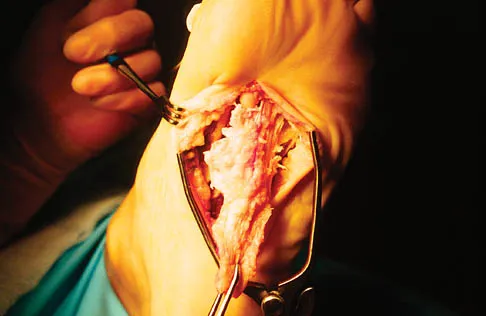

A 56-year-old woman has a painful mass on the bottom of her left foot, and orthotic management has failed to provide relief. Examination reveals that the mass is contiguous with the plantar fascia. An MRI scan shows a homogenous nodule within the plantar fascia. Resection of the tumor is shown in the clinical photograph in Figure 39. What type of cell is most likely responsible for the formation of this tumor?

The history, examination, and surgical findings are most consistent with plantar fibromatosis. Plantar fibromatosis is a benign tumor of the plantar fascia that consists chiefly of fibromyoblasts. These cells produce excessive collagen and are similar to the cells found in the palmar fascia of patients with Dupuytren's contracture of the hand. The myocyte, synovial cell, and osteocyte all produce their respective individual tissue types but do not contribute to the formation of a plantar fibromatosis. The T-cell is an important immunologic cell that is most affected in patients with HIV.